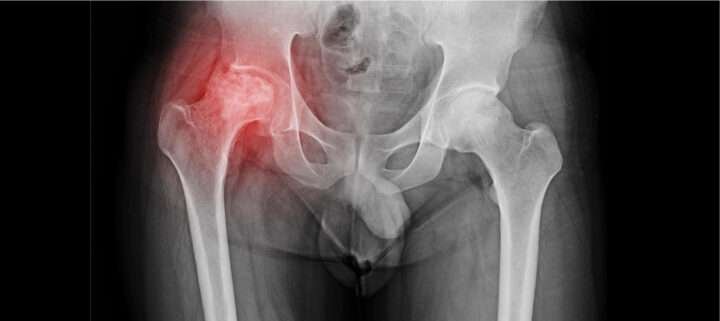

Avascular necrosis (AVN), also known as osteonecrosis, is a serious bone condition where blood supply to a bone is reduced or completely cut off. Without proper blood flow, bone tissues start dying, which may lead to bone collapse. The condition mostly affects the hip joint but can also occur in the shoulder, knee, and ankle.

AVN is a progressive disease that weakens bones and joints. When blood flow to a bone is blocked, bone cells cannot survive, leading to small fractures and eventual collapse of the joint.

Diagnosis of Avascular Necrosis

Doctors usually diagnose AVN through:

- X-rays

- MRI scans

- CT scans

- Bone scans

Early diagnosis can help prevent joint collapse.